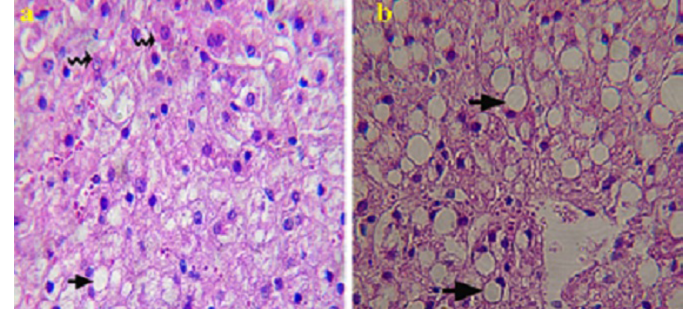

Histopathological picture of liver specimen obtained by biopsy from PT does

A: showing mild macro vesicular fatty change (arrow) and numerous normal hepatocytes (zigzag arrow) (good prognosis); B: showing severe vesicular fatty change (arrow) and less normal hepatocytes (bad prognosis). H & E Χ 1200